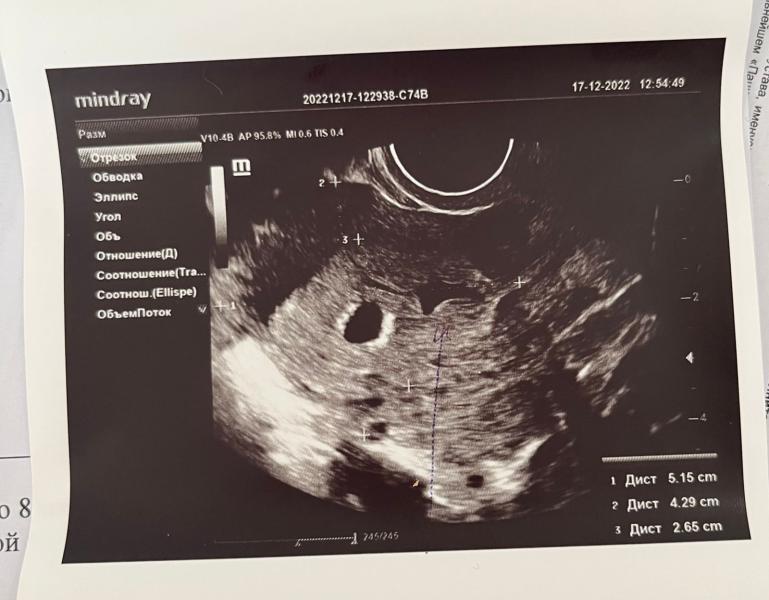

Беременность есть, 3 недели. Но есть маленькая угроза🥺 Гематома.

Сказали должна рассосаться эта гематома после приема утрожестана и на повторное узи через 3-5 недель. Я не понимаю почему приложение показывает такой большой срок и эмбриона если по факту там только 8мм.

У меня срок поставили 4-5 недель в ровно 5 недель по Мемячным когда я пришла. ПЯ было 4,7 эмбрион 1,2 мм